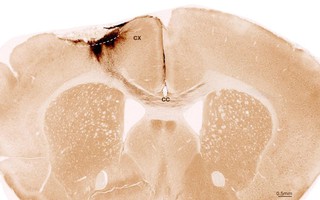

(NLĐO) - Thí nghiệm của các nhà khoa học Mỹ và Thụy Sĩ đã vạch ra con đường mới để phát triển các phương pháp giúp người bị đột quỵ phục hồi tổn thương não.